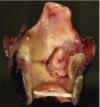

frontal sinus mucocele (empyema) secondary to sinusitis